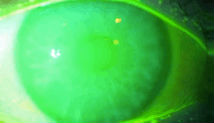

還有一個(gè)可以用來(lái)判斷干眼癥的指標(biāo):淚膜破裂時(shí)間(B.U.T.),也就是眨眼后保持睜眼狀態(tài),淚膜表面出現(xiàn)第一個(gè)干燥裂痕的間隔時(shí)間,即淚膜在眼睛表面停留、維持的時(shí)間。正常情況下,淚膜破裂時(shí)間10秒;如果,淚膜破裂時(shí)間10秒,即提示淚膜穩(wěn)定性下降,可能引起干眼癥。

淚膜破裂時(shí)間測(cè)定:

1、角膜熒光素納染色

2、計(jì)算淚膜破裂時(shí)間